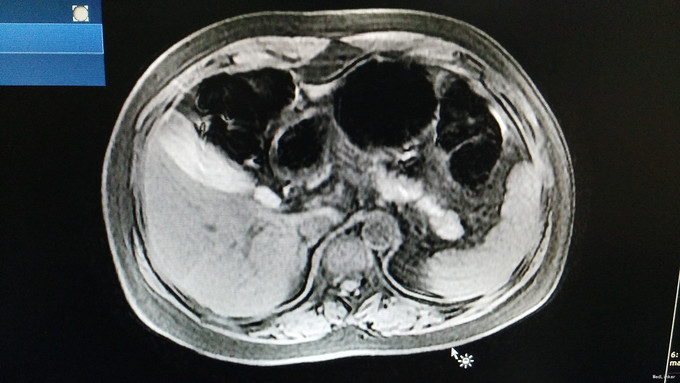

诊断为:低血糖症, .治疗:针对低血糖症:监测血糖,防止患者因低血糖发生意外。 2.针对胰腺占位性病变(胰岛素瘤可能性大):建议转入胰腺外科手术治疗,病情变化随诊。